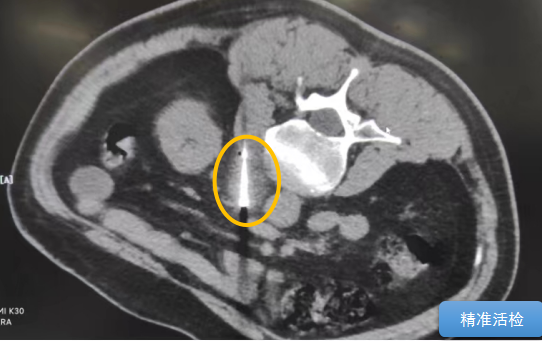

經(jīng)過多學科討論,陳寶瑩主任根據(jù)影像資料指出,患者轉(zhuǎn)移瘤位于腹膜后,內(nèi)側瀕臨人體最大的血管——主動脈;前方同樣有血管緊貼腫瘤;外側是腎臟,后方是椎體和神經(jīng),夾縫中進針難度大,治療時要避免周圍重要臟器、血管和神經(jīng)的損傷,因此可以選擇CT引導下精準穿刺活檢同步冷凍消融治療,即獲得病理組織有利于下一步全身治療方案的調(diào)整,同時殺死腹膜后轉(zhuǎn)移瘤,周圍正常組織損傷的可能性也小。

術中陳寶瑩主任、李鐵柱教授、兀云飛醫(yī)生、魏東紅技師、汝平護士協(xié)調(diào)配合,夾縫進針難度雖大,但在CT引導下逐步進針,精準到位,順利活檢取得組織,由于腫瘤較大,為了提高消融效率,平行置入兩根冷凍消融針,同時啟動冷凍消融,術中清晰觀察到冰球完全覆蓋病變,患者沒有任何不舒服,治療中還可以和醫(yī)生聊天。